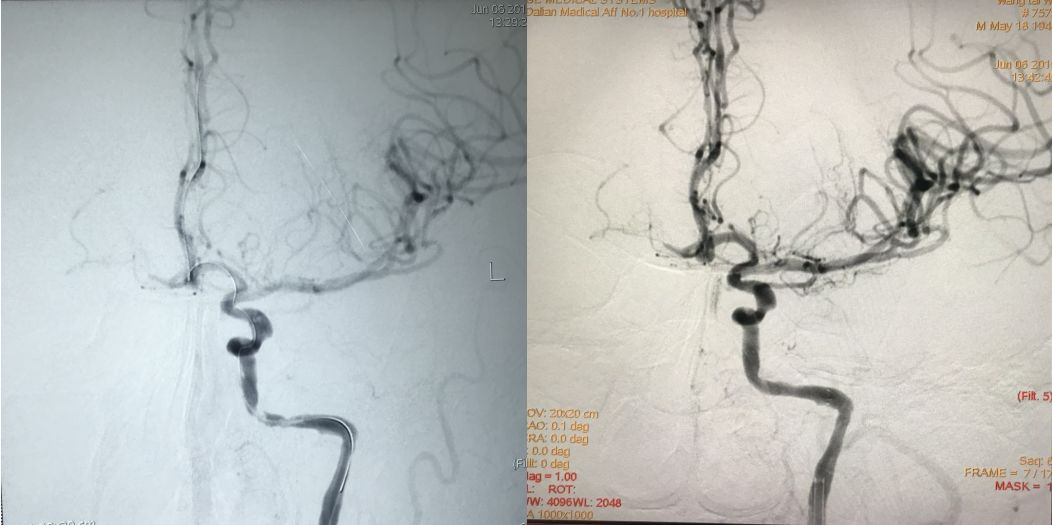

外院DSA如下图:

DSA示右侧颈内动脉起始部严重狭窄。

左侧颈内动脉岩骨段严重狭窄。

左侧颈内动脉岩骨段狭窄支架置入术。